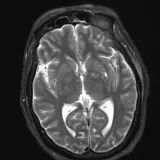

PACS์—์„œ ๊ธฐ๋Œ€ํ•  ์ˆ˜ ์žˆ๋Š” ๋ชจ๋“  ๋„๊ตฌ๋ฅผ ๊ฐ–์ถ˜ ์™„์ „ํ•œ ์ธํ„ฐ๋ž™ํ‹ฐ๋ธŒ ์ฆ๋ก€ — ์Šคํฌ๋กค, ์œˆ๋„์šฐ ์กฐ์ ˆ, ํ™•๋Œ€/์ถ•์†Œ, ํŒจ๋‹, ๊ณ„์ธก, ROI, ์ „์ฒด ํ™”๋ฉด ๋ชจ๋“œ๊นŒ์ง€ ์ง€์›ํ•ฉ๋‹ˆ๋‹ค.

์‹ค์ œ PACS ์›Œํฌ์Šคํ…Œ์ด์…˜์ฒ˜๋Ÿผ ์Šคํฌ๋กค, ํŒจ๋‹, ์œˆ๋„์šฐ ์กฐ์ ˆ, ํ™•๋Œ€/์ถ•์†Œ๊ฐ€ ๊ฐ€๋Šฅํ•ฉ๋‹ˆ๋‹ค